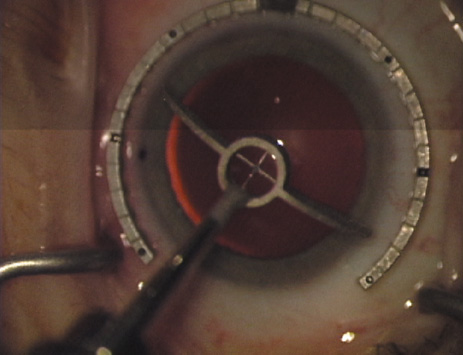

Case 3 is a 48-year-old bilateral hyperope who presented for a refractive surgical consultation. The refraction in his left eye was found to be +3.25 +1.75 × 85. Keratometry was somewhat flat but confirmed WTR cylinder as did corneal topography. Based upon the patient's age, refraction, and somewhat shallow anterior chambers, the decision was made to proceed with a refractive lens exchange. The NAPA nomogram called for LRIs of 55 to 60 degrees with intraoperative pachymetry. Intraoperative keratoscopy confirmed the steep 85-degree meridian (Figs. 2029).

Fig. 20. Keratoscopy, after lifting of the speculum to relieve induced pressure and distortion of the corneal mires, confirms the steep axis of 85 degrees.

Fig. 21. The broad hash marks of the fixation ring are centered just off of the 6:00 limbal orientation mark, over the 85 degree meridian in this left eye. The two cut RK marker is positioned at one extent of the LRI, just under 30 degrees from the central steep meridian and the cornea is marked.

Fig. 22. A second mark is made delineating the opposite extent for a total arc length of just under 60 degrees.

Fig. 23. Following pachymetry measurement over the entire arc length of the incision, an adjustable micrometer diamond knife is set to 90% of the thinnest reading obtained.

Fig. 24. The inferior incision is begun.

Fig. 25. The incision is completed for a total arc length of just under 60 degrees.

Fig. 26. The opposing superior LRI is begun.

Fig. 27. The incision is completed at the corneal mark.

Fig. 28. 6A side-port incision is created for the surgeon's non-dominant right hand, taking care not to intersect the LRI.

Fig. 29. The single-plane RLE incision is completed.